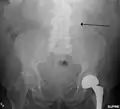

The faint outline of the calcified wall of an AAA as seen on plain X-ray